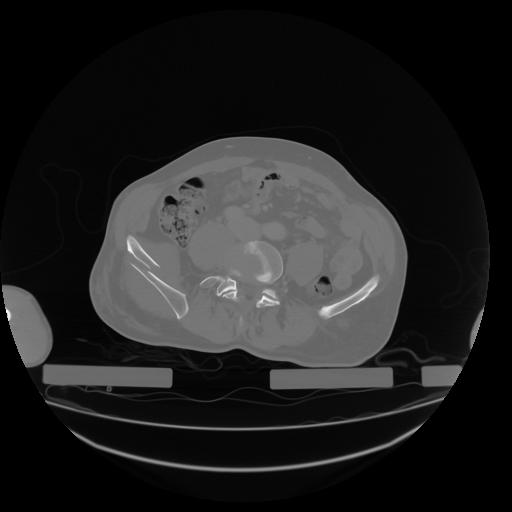

27 CUERPO,CE,Axial,3.0,CUERPO,,